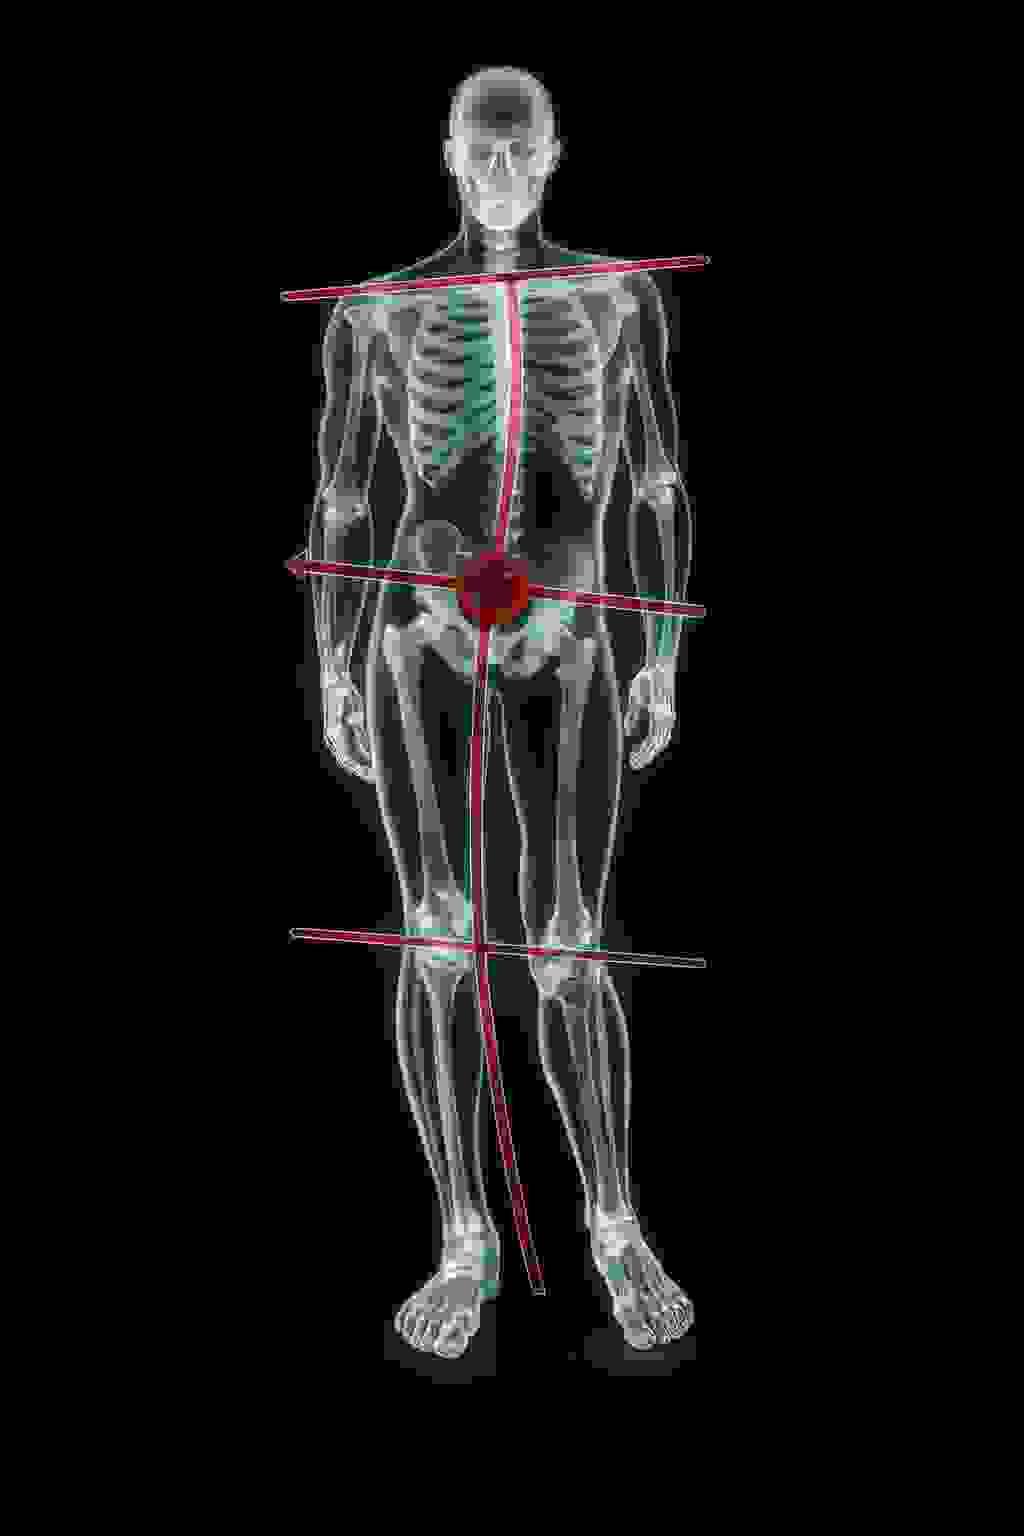

Unequal Weight Bearing: The Hidden Cause of Pain and Dysfunction

Imagine that you are bearing 5, 10, or even 15 kilograms more on one lower limb than on the other. There are several basic clinical tests that help identify the cause of this dysfunction (unequal weight bearing between the lower limbs). It is important to consider dysfunctions that may exist in:

- Muscles

- Ligaments

- Nerves

- Blocked joints

Shoulder asymmetry is not yet a true postural defect—it is rather a deviation / faulty posture. Lowering of one shoulder compared to the other may be linked to careless posture, incorrect habits, or spending too much time in a sitting position. The first symptom that should concern us is back pain and tension. Over time, joint cartilage degeneration may occur. A common cause is pelvic rotation.

The pelvis plays a key role in spinal alignment. Due to a long-lasting incorrect pelvic position, permanent changes may develop in the lumbar, thoracic, and cervical spine. As a result, irreversible damage to intervertebral discs, facet joints, or hip and knee joints may appear, causing pain.

The pelvis is also closely related to body symmetry. It carries the entire vertebral column and has a direct connection with the lower spine and lower limbs. Because of that, any movement of the pelvis results in changes in vertebral position and affects lower-limb movement.